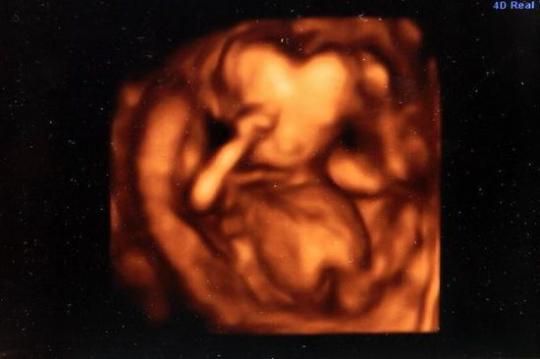

【环球网综合报道】据英国《镜报》12月10日报道,一20岁女子贝弗利·温特(Beverley Winters)在16周孕期时使用3D技术扫描孕检,竟发现腹中婴儿的头部呈心形,然而孩子顺利出生后并无异常。

据悉,贝弗利和她的老公本·普拉特(Ben Platt)都是20岁,之前流过产的贝弗利很看重这次怀孕。贝弗利表示:“我们真的很想要这个孩子,特别害怕孩子的头型影响了他的健康。当得知并无大碍时,我们为爱心型的图像而感动,并珍藏了这个影像。”

据医生透露,孕检时的头部呈心形属于正常现象,因为当时婴儿还在发育,尚未成型。再者,由于3D扫描角度的问题,头的一部分被母体中的液体遮挡了也有可能。